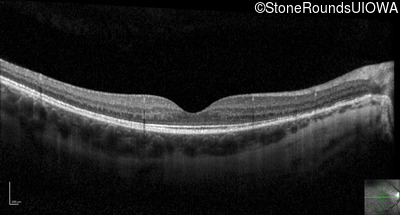

Optical Coherence Tomography - Right - 20/25

Exemplar / OCT Stack